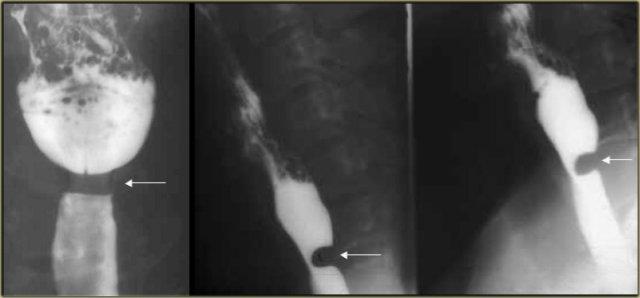

Bên trái là một bệnh nhân khác bị achalasia.

TRÁI: Thực quản giãn (mũi tên) được chiếu phía sau nhĩ phải. GIỮA và PHẢI: Hẹp thuôn nhẵn ngay trên cơ hoành (mũi tên).

Trong quá trình soi huỳnh quang, quan sát thấy một số nhu động với hình ảnh hẹp thuôn nhẵn điển hình ngay trên cơ hoành (mũi tên).